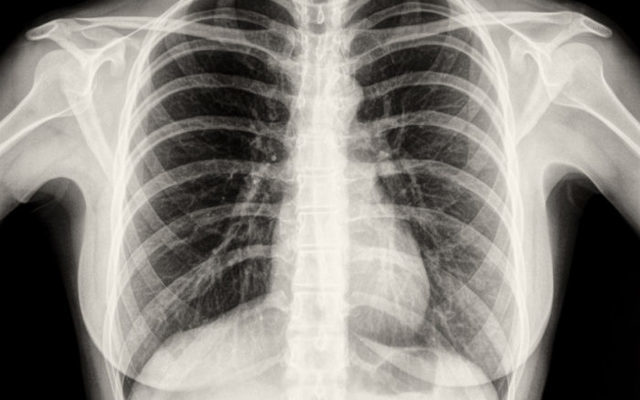

Флюорография — это диагностический тест, направленный на выявление первых симптомов респираторных заболеваний: пневмонии, туберкулеза, кистозной гиперплазии и злокачественных новообразований.

При подозрении на патологию (после флюорографии) пациента направляют на дополнительное обследование — рентген легких. Различия между этими методами.

Информативное обследование выявляет неспецифические изменения легочного интерстиция с фиброзом, утолщением плевры при мезотелиоме, пневмотораксе, пневмотораксе и других серьезных патологических процессах.

Флюорография до сих пор остается информативным методом диагностики раннего туберкулеза легких. Обследование — это обычное обследование, которое тесно связано с высокой заболеваемостью.